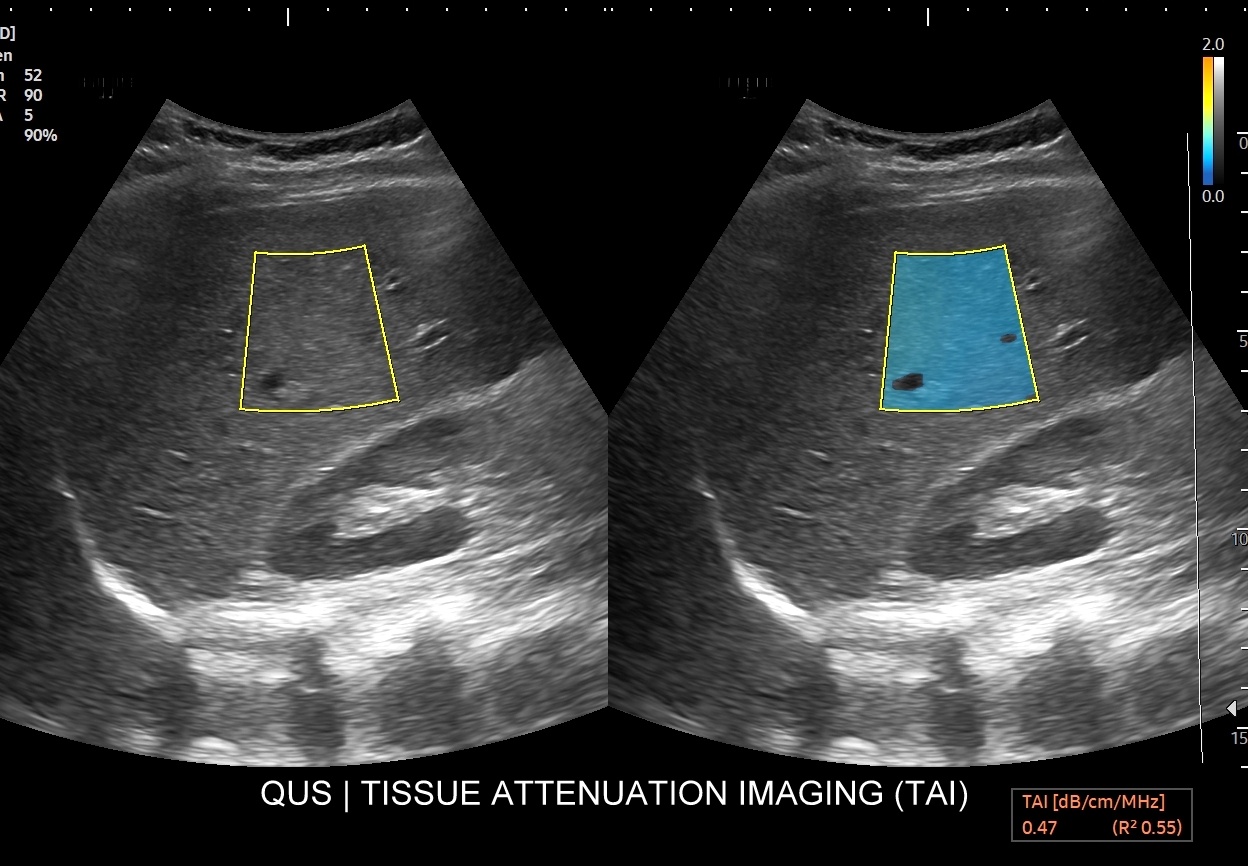

- Ilościowa ocena stłuszczenia wątroby QUS.

Multiparametryczne badanie USG (MPUS) jest rozwinięciem klasycznego USG jamy brzusznej zwykle w formie jednoczasowego zastosowania różnorodnych technologicznie trybów obrazowania USG, zarówno tzw. „nowych”, jak i „starych”. Wśród nowych najważniejszym jest obrazowanie mikrounaczynienia (MVI / MVF), a w dalszej kolejności tryby elastograficzne oraz metody ilościowej oceny stłuszczenia wątroby. Wymienione „nowe” modalności w połączeniu ze „starymi”, przede wszystkim z Dopplerem spektralnym i color-Dopplerem, stanowią rdzeń nowoczesnej ultrasonografii MPUS, gdyż umożliwiają pozyskanie znacznie większej ilości informacji z badania USG w porównywalnym przedziale czasowym, a przez to uzyskanie jego większej wartości diagnostycznej. Przykładowo badanie MPUS umożliwia różnicowanie pseudoguzów od guzów prawdziwych, ocenę żywotności tkanek, biologii nowotworów, funkcjonalną ocenę nerek i wątroby, poprawia obrazowanie dużych naczyń krwionośnych oraz charakterystykę podejrzanych torbieli.